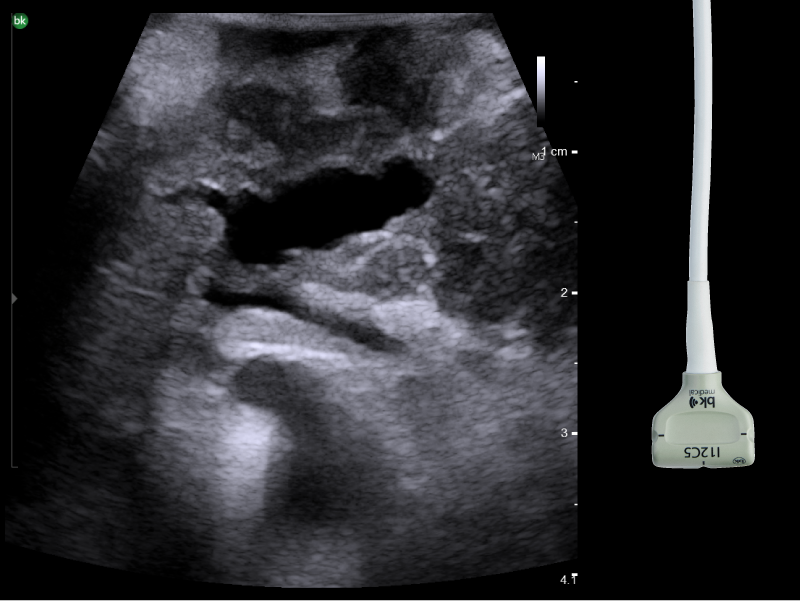

Liver mass, visualized with I-Shaped Transducer